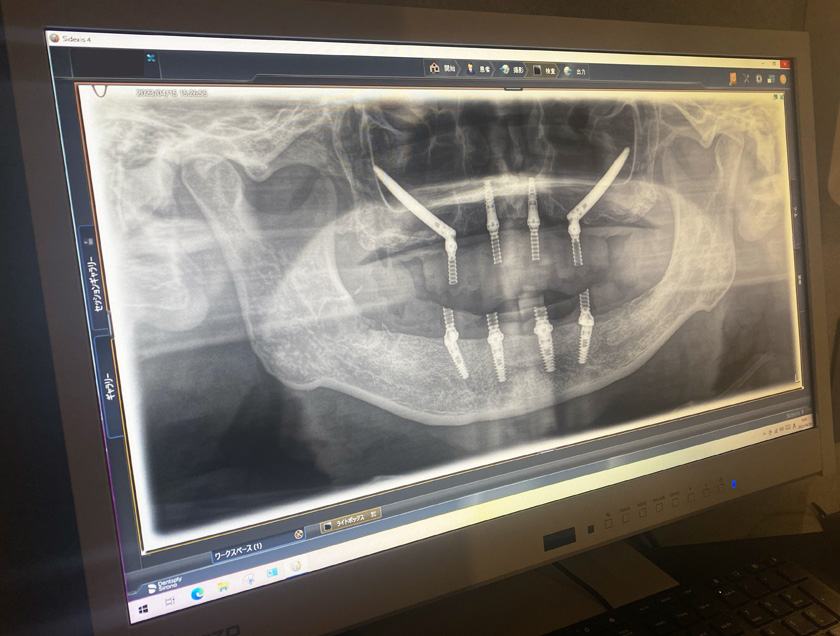

内容 :上下顎オールオン4ザイゴマ4

費用 :5,500,000円

※モニター価格

期間 :半年

リスク:出血・腫れ・痺れ・痛み